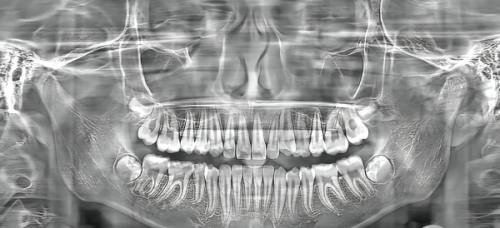

重庆维乐口腔采用了数字化矫正技术,这可是现在特别精良的技术哦。它的优势在于精细度和疗效都特别好。通过 3D 模拟,医生就好像有了一个“透视眼”,可以更正确地制定个性化的矫正方案。打个比方,就像给每个人量身定制一件衣服一样,确保每位患者都能得到适合自己的治疗。而且啊,这种数字化矫正技术能够在较短的时间内起效,特别多患者在几个月内就能看到明显的结果。对于那些追求效率的青少年和大学生来说,这简直就是一个巨大的吸引力。想想看,不用等太长时间就能看到牙齿变整齐,多让人开心啊,这也充分体现了重庆维乐口腔矫正好用。

医院采用 3D 口腔扫描、数字化模拟矫正等数字化技术,为患者提供量身定制的牙齿矫正方案。患者普遍反映,医院的矫正方案针对性强,矫正过程舒适,矫正疗效显著,大大提升了生活质量。比如说,有的患者牙齿拥挤,通过数字化模拟,医生就能提前看到矫正后的成效,然后制定出更适合的方案,让牙齿慢慢变得整齐美观。这种个性化的诊疗方案,让每一位患者都能得到更贴心的治疗,也让大家觉得重庆维乐口腔矫正好用。